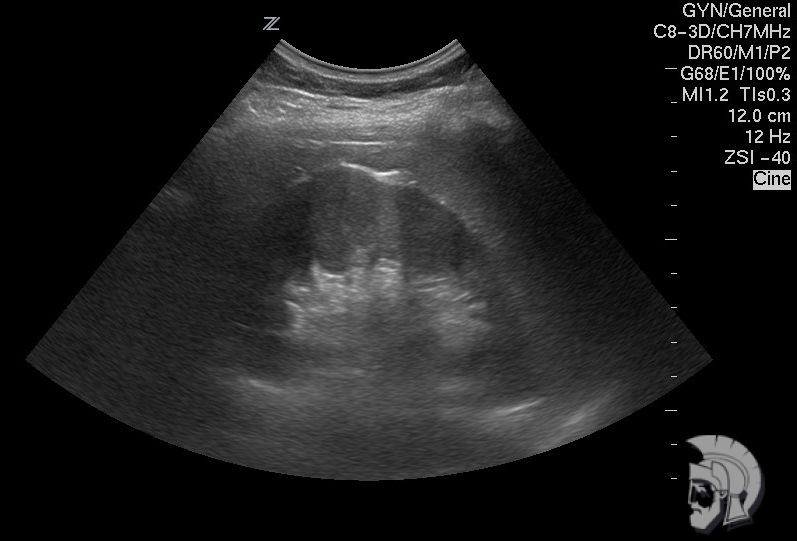

Обратите внимание на совершенное качество фотографий, свидетельствующих об экспертном классе аппаратов УЗИ!

Использование ультразвуковых аппаратов экспертного класса с режимами энергетического допплера и цветового ДОППЛЕРа позволяет врачам Курортной клиники мужского здоровья выявлять патологические изменения почек и мочевого пузыря на ранних этапах.